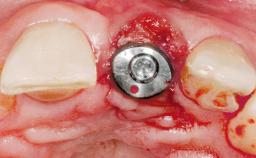

Immediate Flapless Placement of an Implant in a Maxillary Left Central Incisor Site

Type of Implants One-Piece

Placement Protocol Immediate implant placement

Tooth Site Maxillary incisor or canine

Socket Morphology Single-root socket